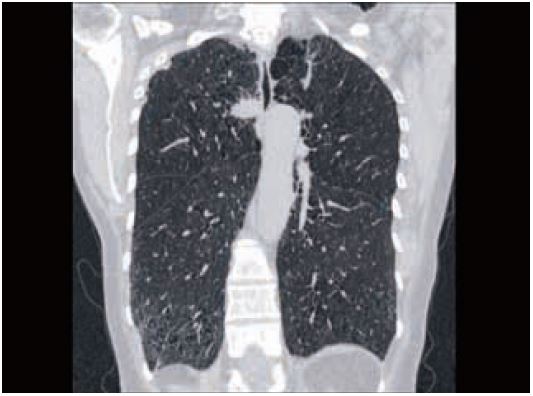

Pис. 6 ТЕЛА та розшарування аорти можна виключити в одній ротації як правило, при <1 мЗв. 30 мл ніопаму 370 при 3 мл/с.

Традиційно при візуалізації з низькою дозою, ділянки, які схильні до фотонного голодування, наприклад через плечі, часто погано візуалізуються. За допомогою детектора PUREViSION ми виявили, що можемо зменшити дозу для звичайних обстеженнь грудної клітки та все ще підтримувати адекватний сигнал/шум, що дозволяє безперешкодно отримати зображення через верхівки легень. Зменшення шуму DAS у цих областях з низьким вмістом фотонів було компенсовано для підтримки загального співвідношення сигнал/шум (рис. 7).

Рис.7 Рутинне сканування легень 0,5 мм. Загальний DLP 46 (0,8 мЗв)